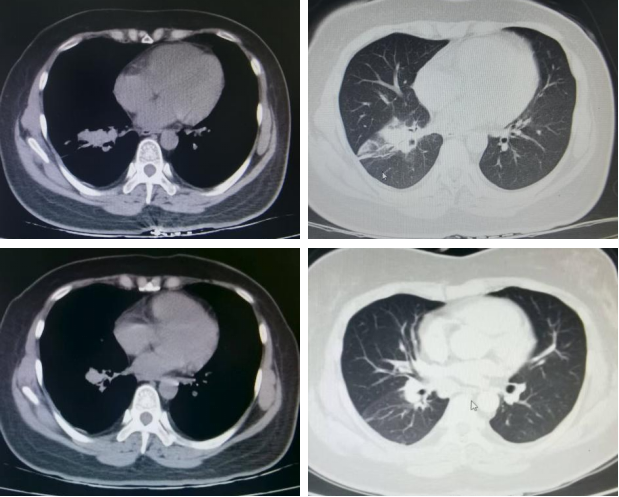

第二阶段:2024年5月29日,胸部CT示右肺下叶团片灶,较前减小。由于患者在使用双膦酸盐后出现严重的发热及骨痛等不良反应,遂将骨保护治疗方案调整为地舒单抗注射液。

第三阶段:2024年9月20日,胸部CT示右肺下叶团片灶、纵隔及右肺门肿大淋巴结,结合病史考虑肺癌并淋巴结转移性肿大,较前片(2024年5月29日)减小。后续治疗方案调整为“PD-1抑制剂单药维持治疗+地舒单抗抗骨转移治疗”。

2025年7月16日:胸部CT示右肺下病灶较前减小。